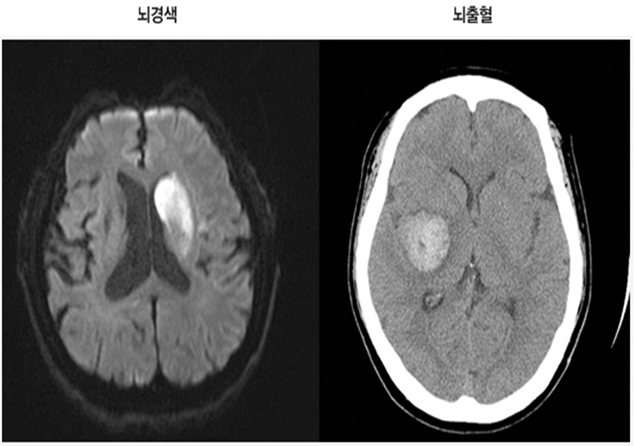

뇌(혈관)질환 검사 안내

MRI/MRA 3.0T

자기장을 이용하여 뇌 구조를 보는 MRI와 뇌 혈관을 보는 MRA.

뇌혈관 CT

X선을 투과하여 뇌의 단면 또는 3차원적인 영상을 통해 뇌 질환 진단.

뇌졸중 (중풍)

뇌혈관 이상으로 갑자기 발생하며, 손발의 마비 증상 및 호흡 곤란 등의 증상이 나타나는 질환입니다.